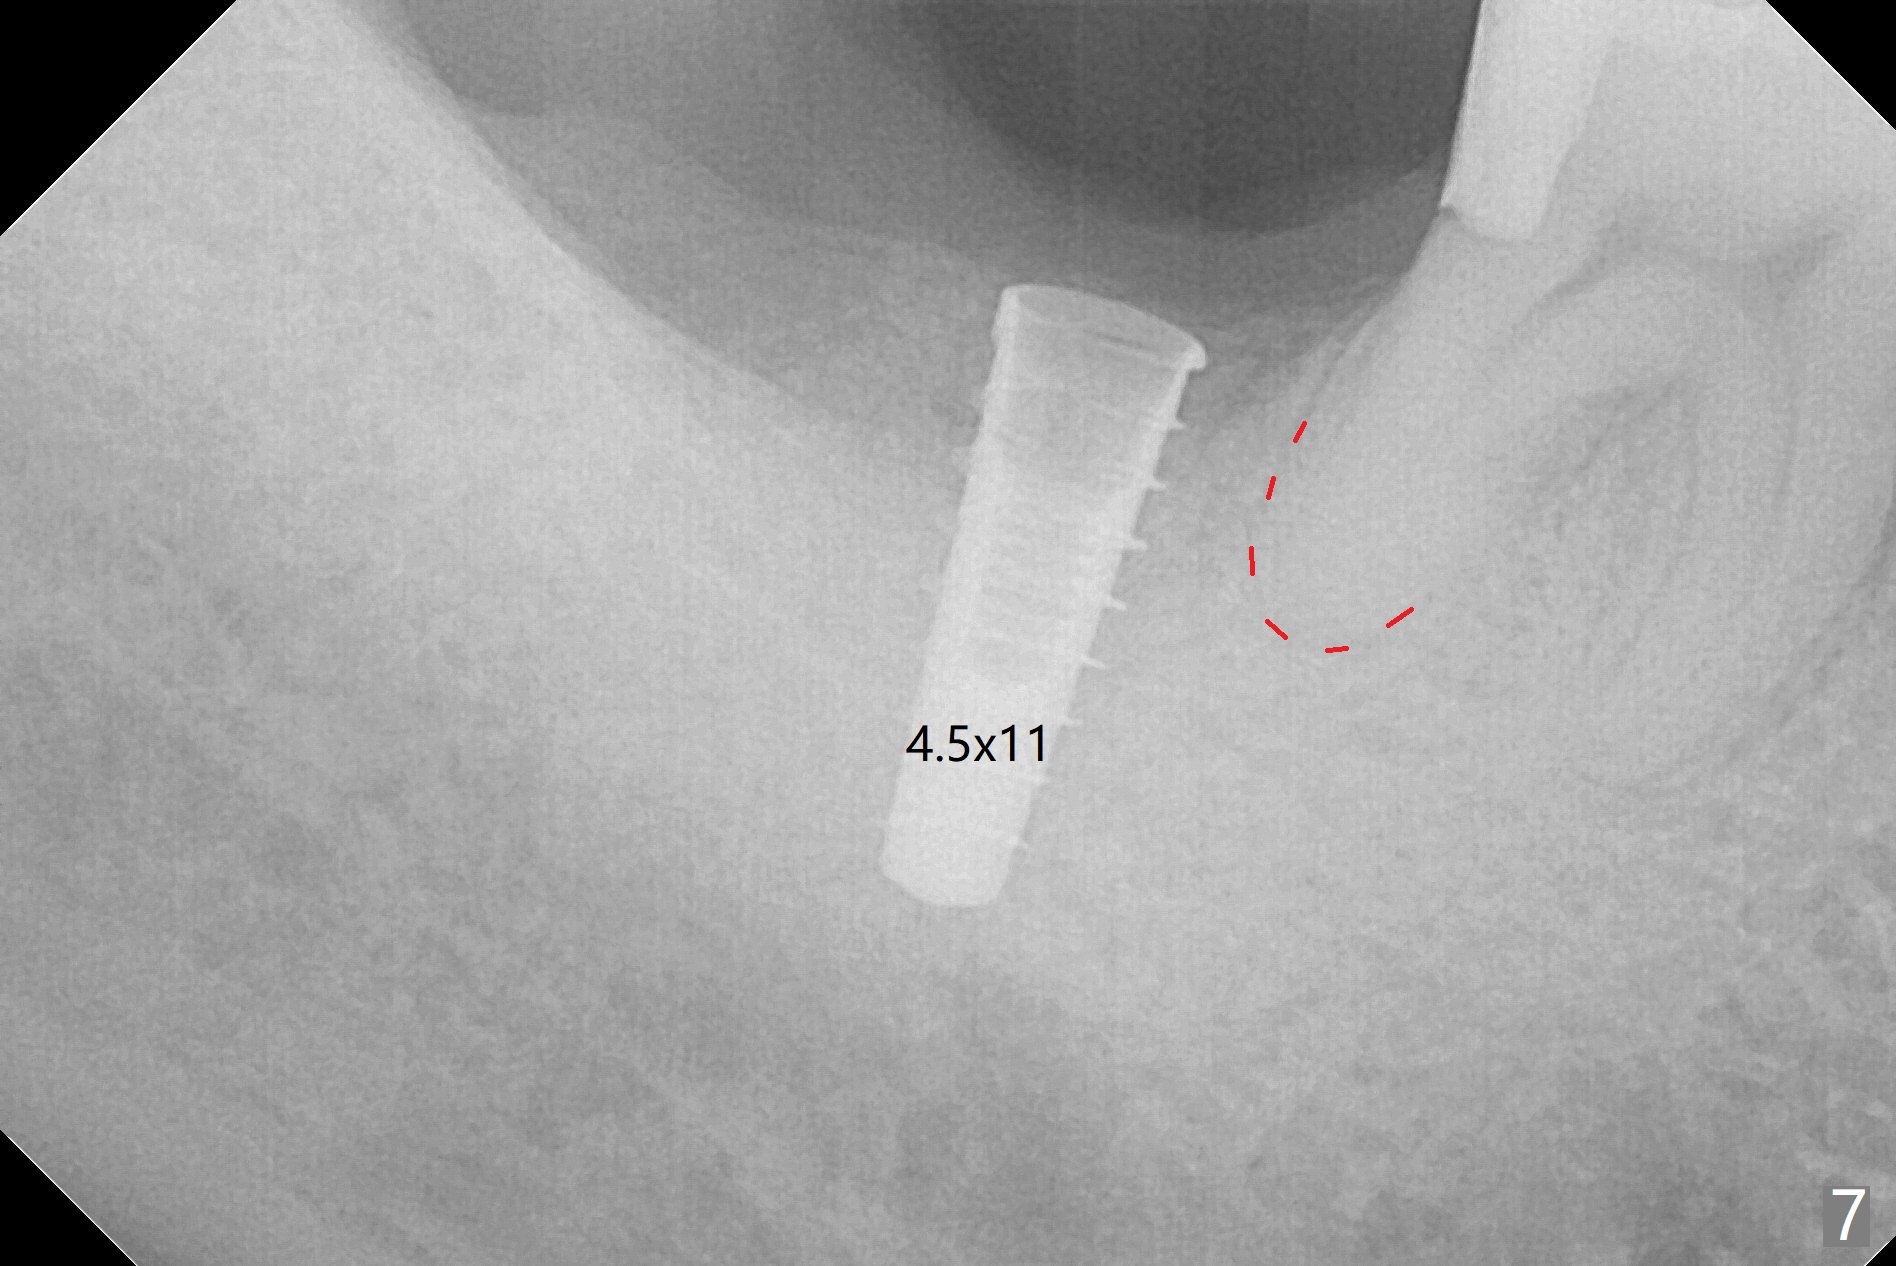

The socket shrinks with buccal plate reduction 3 months post socket preservation (Fig.5), as compared to 10 days postop (Fig.4). To restore the socket as much as possible, Magic Split is used (flapless), followed by Magic Expanders 3-3.8 mm for 11 mm (gingival level) and a 4x11mm dummy implant (Fig.6). The osteotomy is moved distal by using Lindamann bur; following 3.8 mm Magic Drill, a 4.5x11 mm dummy implant (Fig.7). Finally a definitive 5.5x9 mm implant is placed with <45 Ncm; a 6x2 mm healing abutment is placed to close the access (Fig.8). Autogenous bone harvested from the Magic Drill returns to the osteotomy mainly buccal prior to implant placement (Fig.8 *). The patient reports no discomfort immediately postop, thanks to the flapless technique. The patient has had postop pain; 11 days postop, the abutment and implant are found to be loose. After re-tightening by hand, the complex is seated deeper and more stable (Fig.9 arrow).